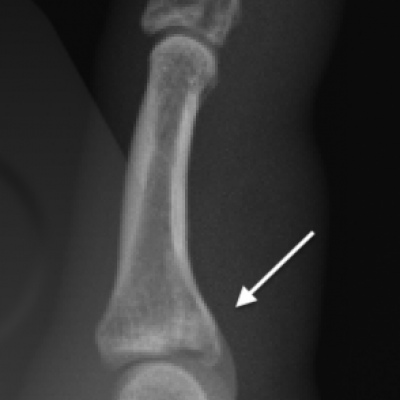

Fracture of the bone is commonly termed a broken bone. Dislocation is where the normal alignment and contact of the joint surfaces is disrupted causing deformity. Dislocations can sometimes spontaneously reduce or require manipulation to put the joint back in to the correct position. Trauma and sports injuries can result in a fracture or dislocation. An X-Ray should be performed to check that the bone and joint position is in adequate and will help guide your doctor’s decision about whether a specialist referral is required.

- Cartilage – Fractures that extend into the joint can injure the smooth cartilage surfaces that cover the bone ends that form the moving parts of the joint. These injuries can lead to a long term risk of arthritis in some cases.